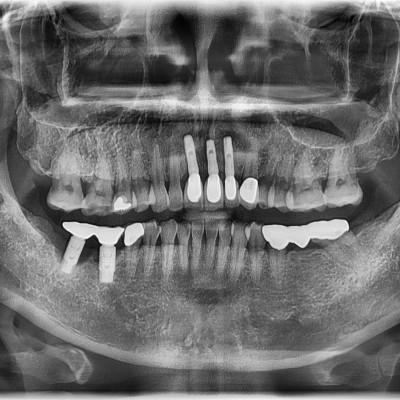

• 9

임플란트 재수술 #24.25 타원임플란트 제거 후 임플란트 재수술 + 치조골 이식술 시행하였습니다.

작성자 이턱이 작성일 01-27 조회 128